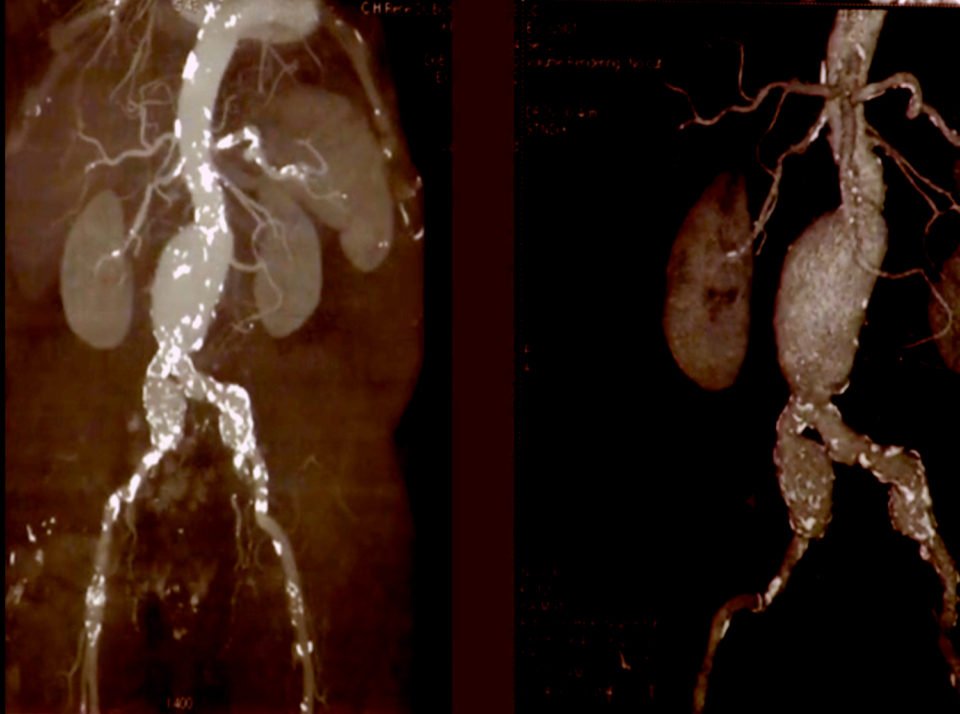

Les examens les plus pertinents dans la prise en charge d’un anévrisme de l’aorte abdominale sont l’échographie Doppler artériel, l’angioscanner de l’aorte et des artères des membres inférieurs et l’angio-IRM.

L’échographie aorto-iliaque est le premier examen à demander pour confirmer le diagnostique. C’est un examen fiable, reproductible, non invasif et peu couteux. C’est l’examen utilisé en pratique courante pour la surveillance des petits anévrysmes et pour le dépistage. Il permet la recherche d’autres anévrysmes au niveau fémoro-poplités.

L’angioscanner aorto-iliaque est plus invasif mais plus reproductible que l’échographie et moins opérateur dépendant. C’est l’examen de choix avant un traitement par endoprothèse ou par chirurgie classique. Il permet les mesures exactes (« sizing ») de l’anatomie de l’anévrysme, de l’aorte et des artères iliaques avant mise en place d’une endoprothèse. Il permet la recherche d’autres anévrysmes au niveau fémoro-poplités et d’étudier l’ensemble de l’aorte.